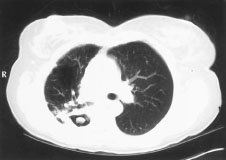

Signo de "creciente aéreo" en la aspergilosis pulmonar tardía

De la colección del Dr. P. Chandrasekar; utilizada con autorización

Ver esta imagen en el contexto de la/s siguiente/s sección/es: